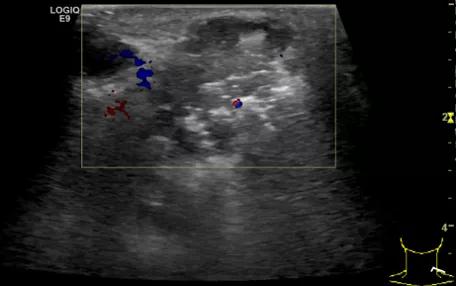

第三例是甲状腺癌患者,双侧甲状腺癌切除术后、碘治疗后一年余效果欠佳,超声显示左颈3区3枚低回声结节,穿刺示甲状腺乳头状癌转移。患者不愿意手术,希望采取局部治疗。对病灶进行液体隔离后采取热消融术,由于淋巴结较小,热消融一分钟左右完全灭活,术后增强影像显示没有脏器充填。

(病例3图例)